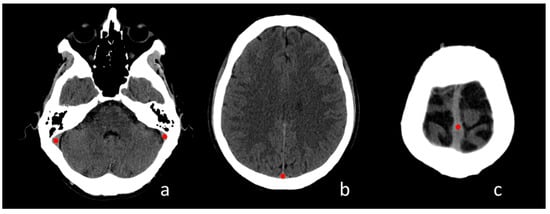

:1. Introduction

2.5. Image Analysis